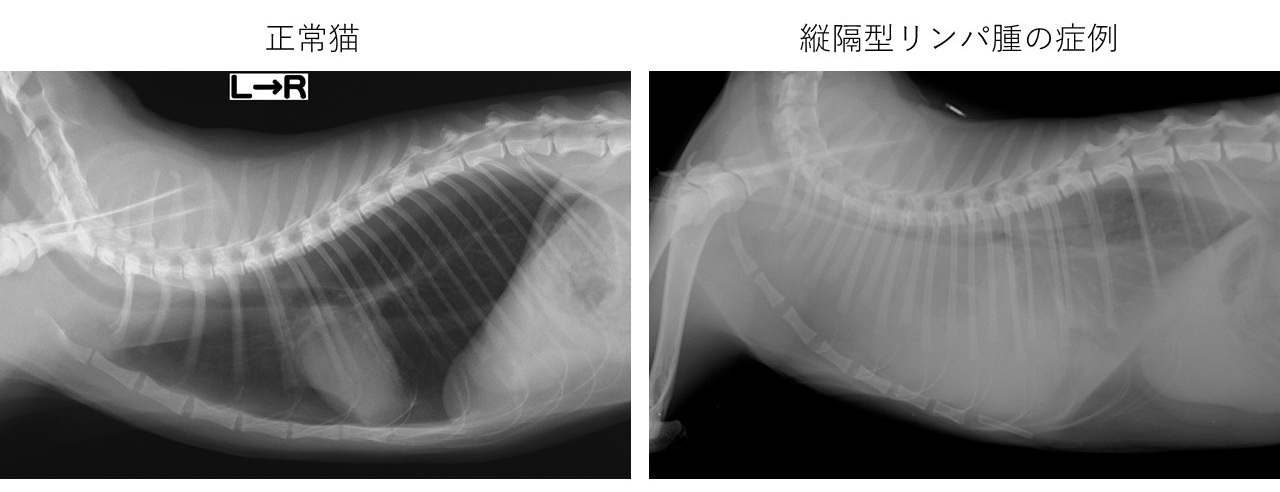

縦隔型リンパ腫の症例。縦隔内に発生した腫瘍の影響で胸水貯留がみられ、胸腔内全体が白くなり心臓の陰影も不明瞭となっている。左は正常な猫の胸部レントゲン画像。